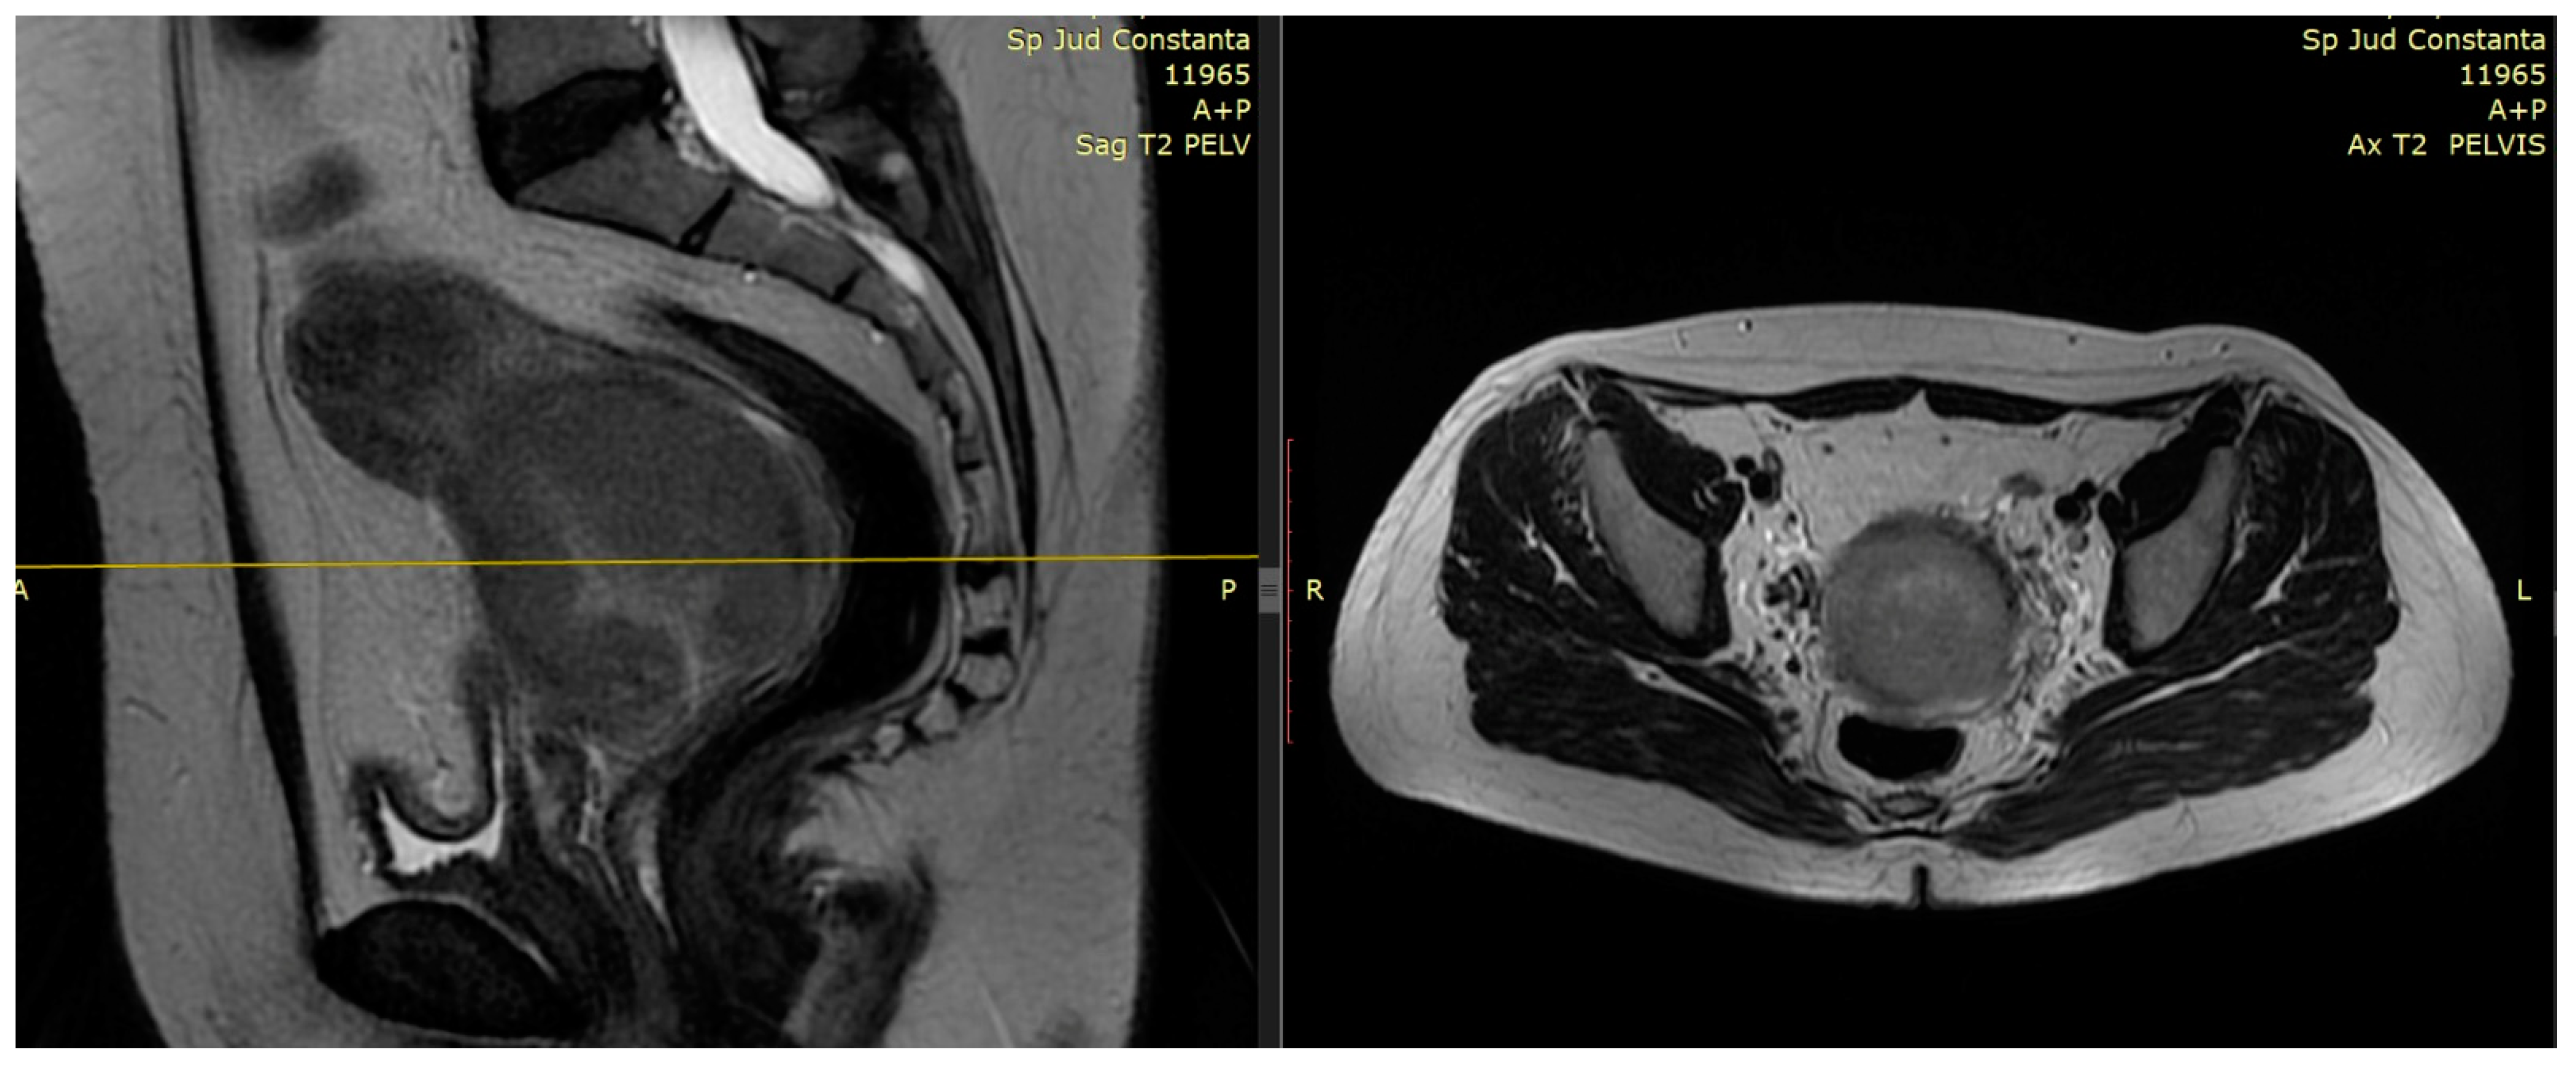

2.1. The Role of MRI